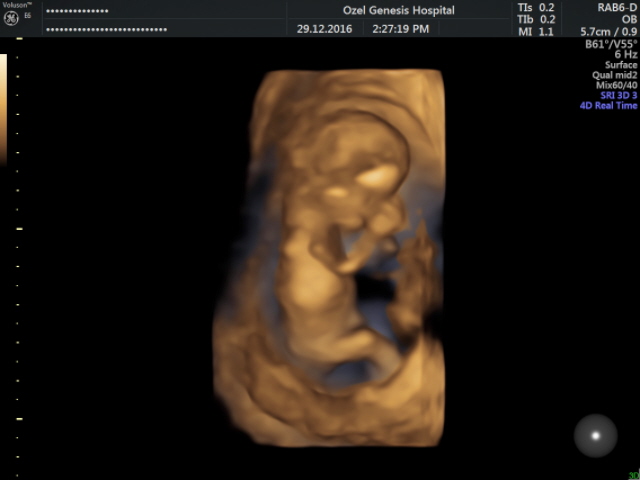

S Sedatunc Yeni Üye Üye 20 Ocak 2017 #146 Mrb bunlari yeni cektim 12 haftalik. Cinsiyetini yorumlar misiniz Moderatör tarafında düzenlendi: 21 Ocak 2017

Sevimli cadı Daimi Üye Üye 21 Ocak 2017 #147 bebeğinizin cinsiyeti kız gibi görünüyor tabi göresel yine net değil yanılabilirim.